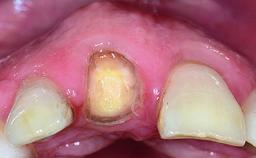

A 32-year-old female Caucasian patient with a compromised maxillary right central incisor was referred to us by a general dentist. Her chief complaints were discomfort and mobility of tooth 11 with unsatisfactory esthetics due to discoloration. The patient reported a previous trauma, some years earlier, as the origin of pathology on the afflicted tooth. Anamnesis was negative for any other dental or periodontal pathology in the remaining dentition. The patient did not take any medication and reported to be a light smoker (5–10 cigs/day). She had high esthetic expectations of her treatment. The extraoral examination revealed a high smile line with full exposure of her maxillary teeth and surrounding soft tissue in the area between the second premolars.

| Abutment Type | Standard |

| Prosthesis Type | FDP |

| Soft Tissue Contour and Volume | Slightly compromised |